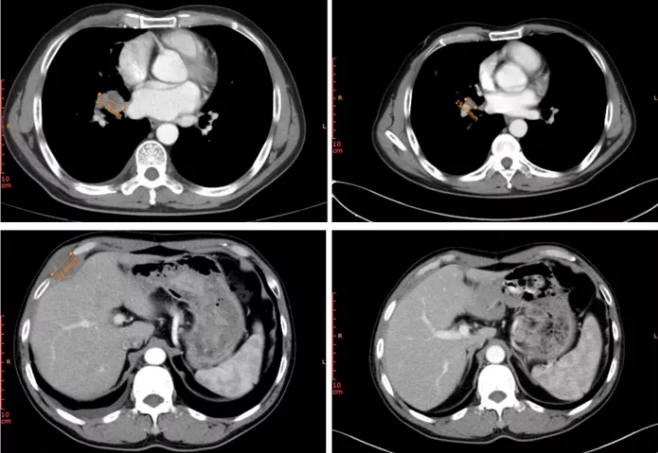

病例2患者为晚期右肺腺癌,接受吉非替尼一线治疗近15个月,进展后接受阿美替尼二线治疗5个月余,疾病再次进展,入组Ⅱ期临床试验,接受MRG003治疗仅2次(6周),靶病灶直径总和缩小50.1%,疗效评估达PR(图2)。

图2. 治疗前(左上:右肺门处病灶;左下:右侧胸壁转移瘤)及治疗后(右上:右肺门处病灶;右下:右侧胸壁转移瘤)病灶变化